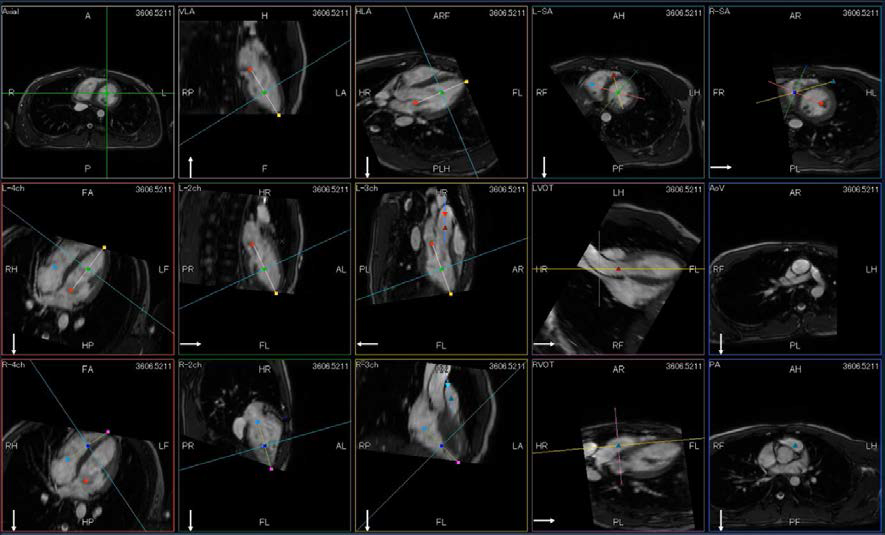

近年、突然死の中で最も多い原因が心疾患とされており、心臓MRI検査はその突然死予防のためにドックへの適応が期待されている。しかし「撮像が難しい」、「検査時間が長い」などが障壁となり、検査がなかなか身近になっていない。cS Editionでは心臓左室位置決めアシスト機能CardioLineにSCMR(Society for Cardiovascular Magnetic Resonance)にて要求されている右室と弁及び流出路などの8断面を加えたCardioLine+を搭載した(図2)。従来、目的の断面を得るために複数回の息止め撮像が必要だが、1回の息止め撮像で14断面を取得することが可能である。これにより検査時間の短縮化、患者さんへの息止め負担を大幅に低減した。

さらに、より一層の簡便化を実現すべく、生体構造の認識技術により被検者の心臓位置を装置が自動で把握するSUREVOITM Cardiacを搭載した。寝台位置設定からMRCA検査の横隔膜同期プローブの設定までの様々な撮像アライメントをアシストすることで、一般的な心臓MRI検査時間の43%を占める操作時間の割合を、9%まで削減する。